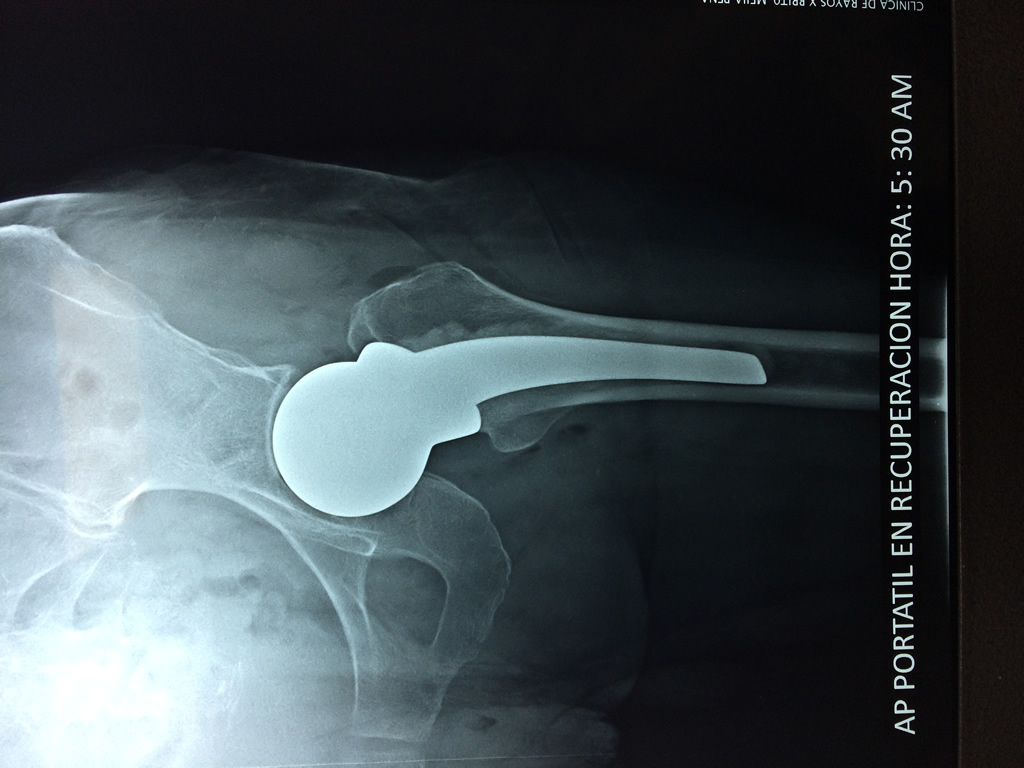

La cirugía de fractura de cadera se realiza para reparar una ruptura en la parte superior del hueso del muslo. Este hueso se denomina fémur.

Es parte de la articulación coxofemoral. Si una fractura de cadera no recibe tratamiento, es posible que deba permanecer en una silla o en la cama.